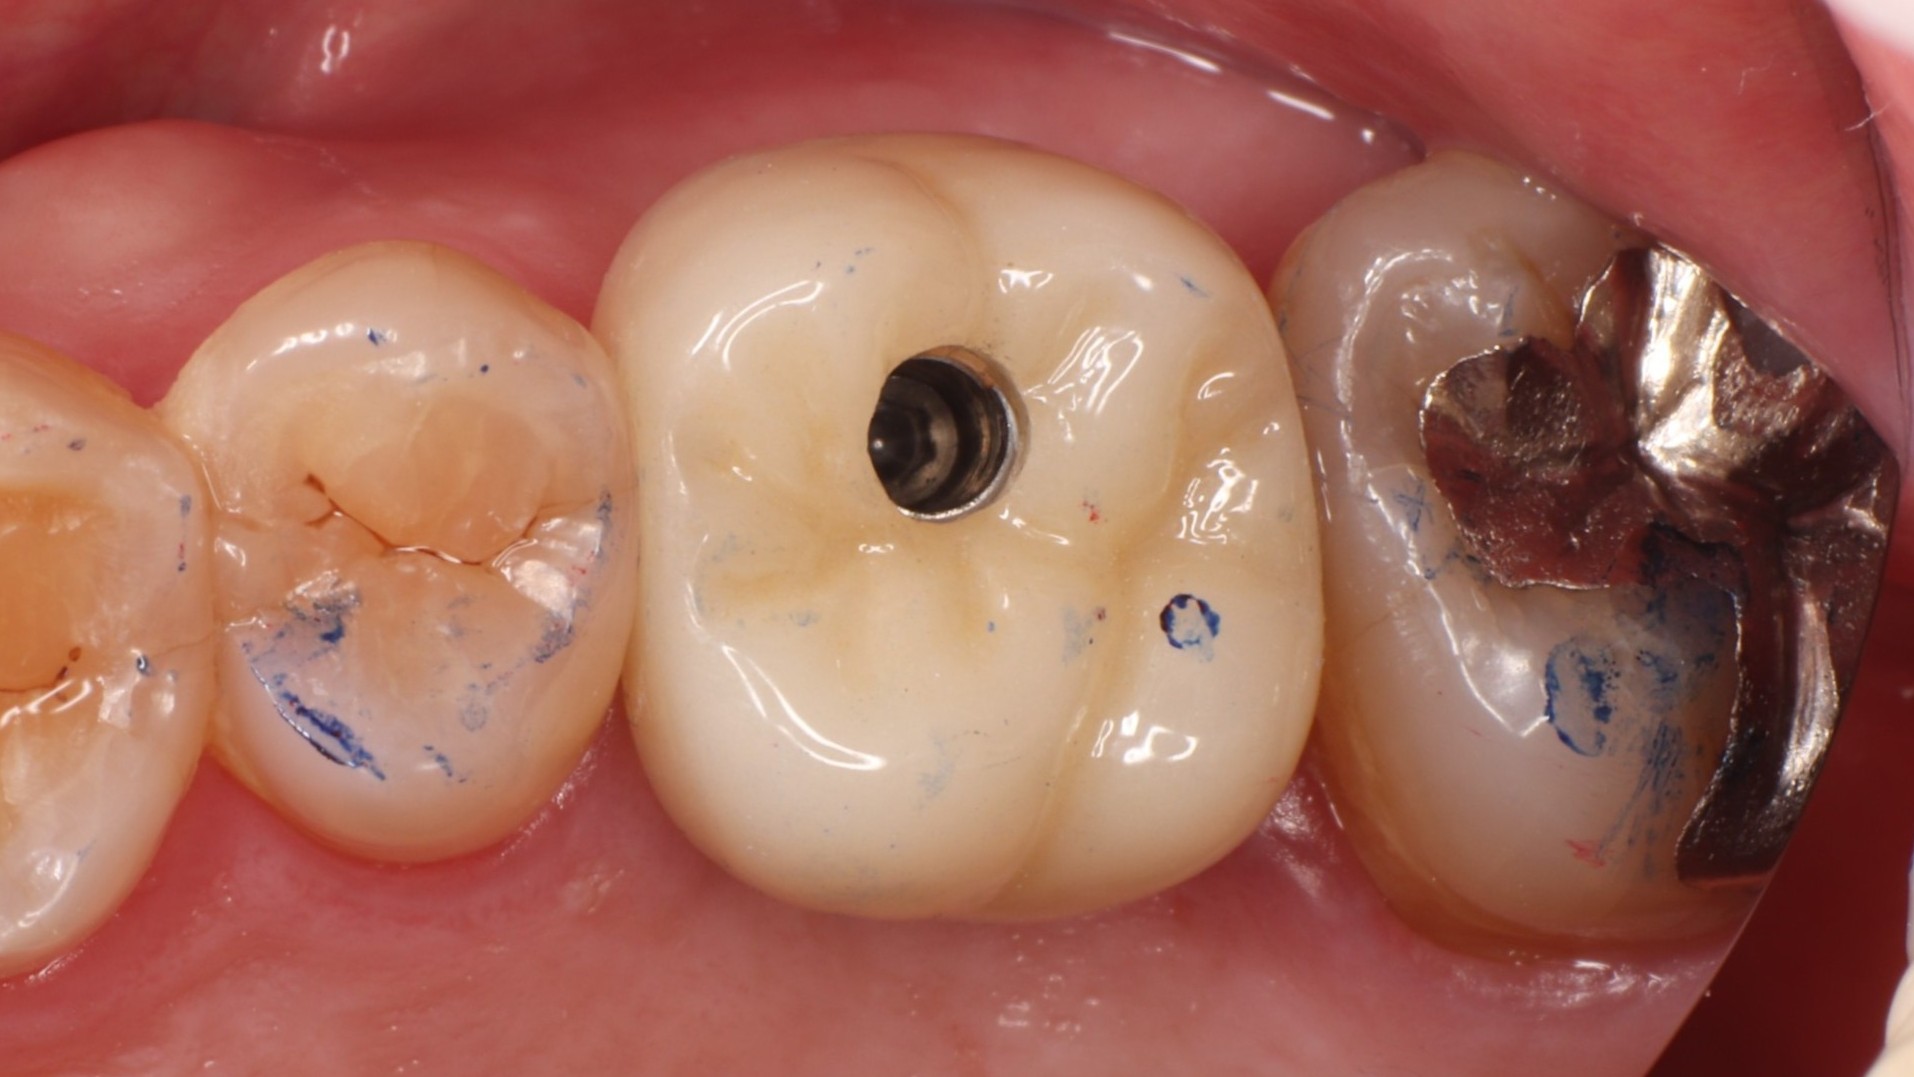

Step 5 最終補綴装着・完成

最終クラウン装着後

最終クラウンを装着して治療完了。周囲の歯と調和した自然な仕上がりで、咬み合わせも安定しています。隣接する天然歯は一切削っていません。